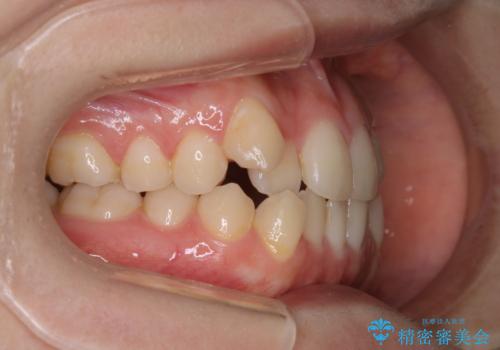

八重歯とクロスバイト:インビザライン治療

- 八重歯が気になるとの事でご相談にいらした方です。

インビザラインで綺麗に並べました。

気になっていた八重歯が綺麗になって大変喜んでいただけました。